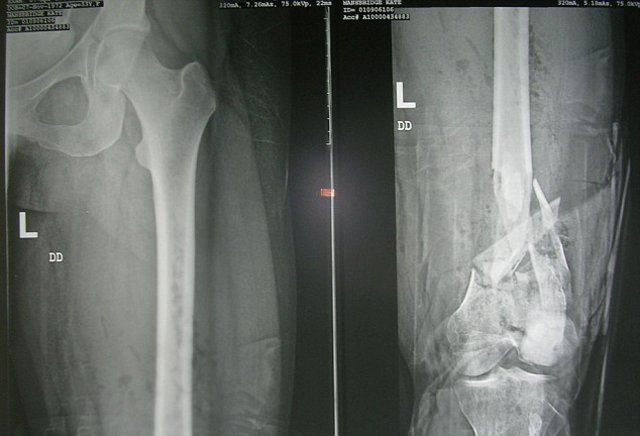

Bir kaç yıl sonra Fransa'da bisiklet sürerken bir arabanın çarpması sonrasında bacakları ezilen ve beyninde hasar oluşan Mansbridge, bir daha yürüyemeyecek hale geldi.

Hatta doktorlar Kate'in tekerlekli sandalyede yaşamını sürdürmek zorunda kalabileceğini belirtti.